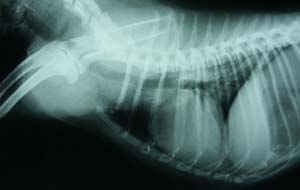

胸部X線所見:心基部に限局した肺胞浸潤影あり、気管虚脱・気道内異物・心陰影異常なし(図2)。

今回、呼吸困難時の胸部X線にて心基部に限局した浸潤影がみられた。この影は治療で完全に消失した。中枢気道の炎症反応に関係あるかもしれない。

図2 初診時胸部X線所見。心基部に限局した浸潤影がみられた。

図4 翌日の胸部X線所見。浸潤影は消失した。